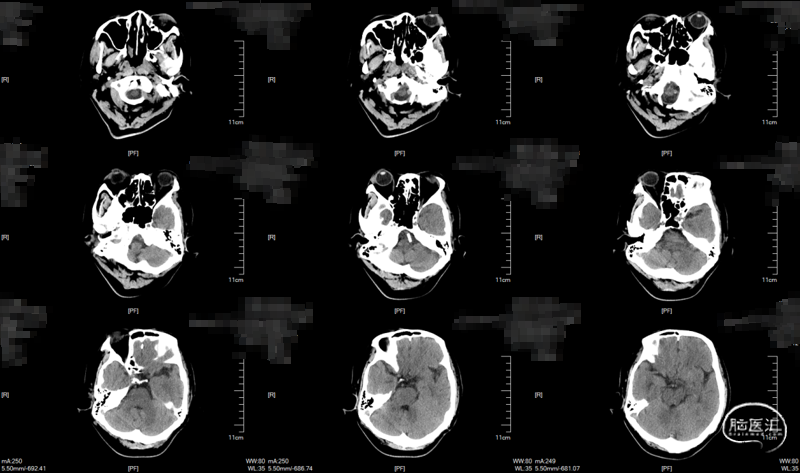

术中DynaCT。

术后4h CT。